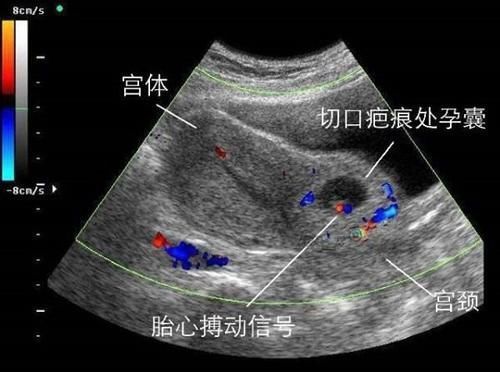

正当她为自己年轻的身体而窃喜时,却突然发现有一个小惊吓,原来以为身体有异样,检查之后发现自己怀孕了。因为头胎是剖腹产,医生嘱咐想要生二胎的话要在三年以后,但是这还没有半年就怀孕,那怎么行呢?

当这个消息被家里人知道后,婆婆气定神闲地告诉她,村里还有人一年做了两次剖腹产,也没见人家有什么危险,医生说话都是吓人的。就这样,网友骆驼就把这个孩子留了下来。但是到了怀孕30周后的一天早上,突然肚子剧痛,当送到医院时,B超显示子宫已经破裂,孩子的脚丫子都伸了出来,腹腔里已经满是鲜血。经过急救,自己的命保住了,但是孩子却没保住,这时她才后悔没有听医生的话。

之所以在第一胎使用了剖腹产之后,要隔上两三年再怀老二,那是因为剖腹产让子宫上面受了伤,那条长长的伤疤虽然表面上看起来已经愈合,但是它里面的组织长得还不够结实。

经过了两三年的修整,才能慢慢的恢复原来的弹性,如果像网友骆驼这样,在一年之内就想要在怀孕,在胎儿成长的过程中,伤疤会因为受不住剧烈的膨胀而崩开。